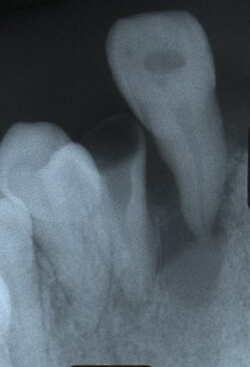

②歯牙損傷

歯牙の損傷には歯牙の破折・嵌入(かんにゅう)・脱臼などがあります。

抜け落ちた歯(歯牙脱臼)を元の位置に戻すことを歯牙再植術と呼び、早期に適切な処置を行えば、十分な機能を果たす可能性が高まります。脱落した歯は無理に洗ったりせず、生理食塩水や牛乳などで乾燥させないようにしてお持ち下さい。